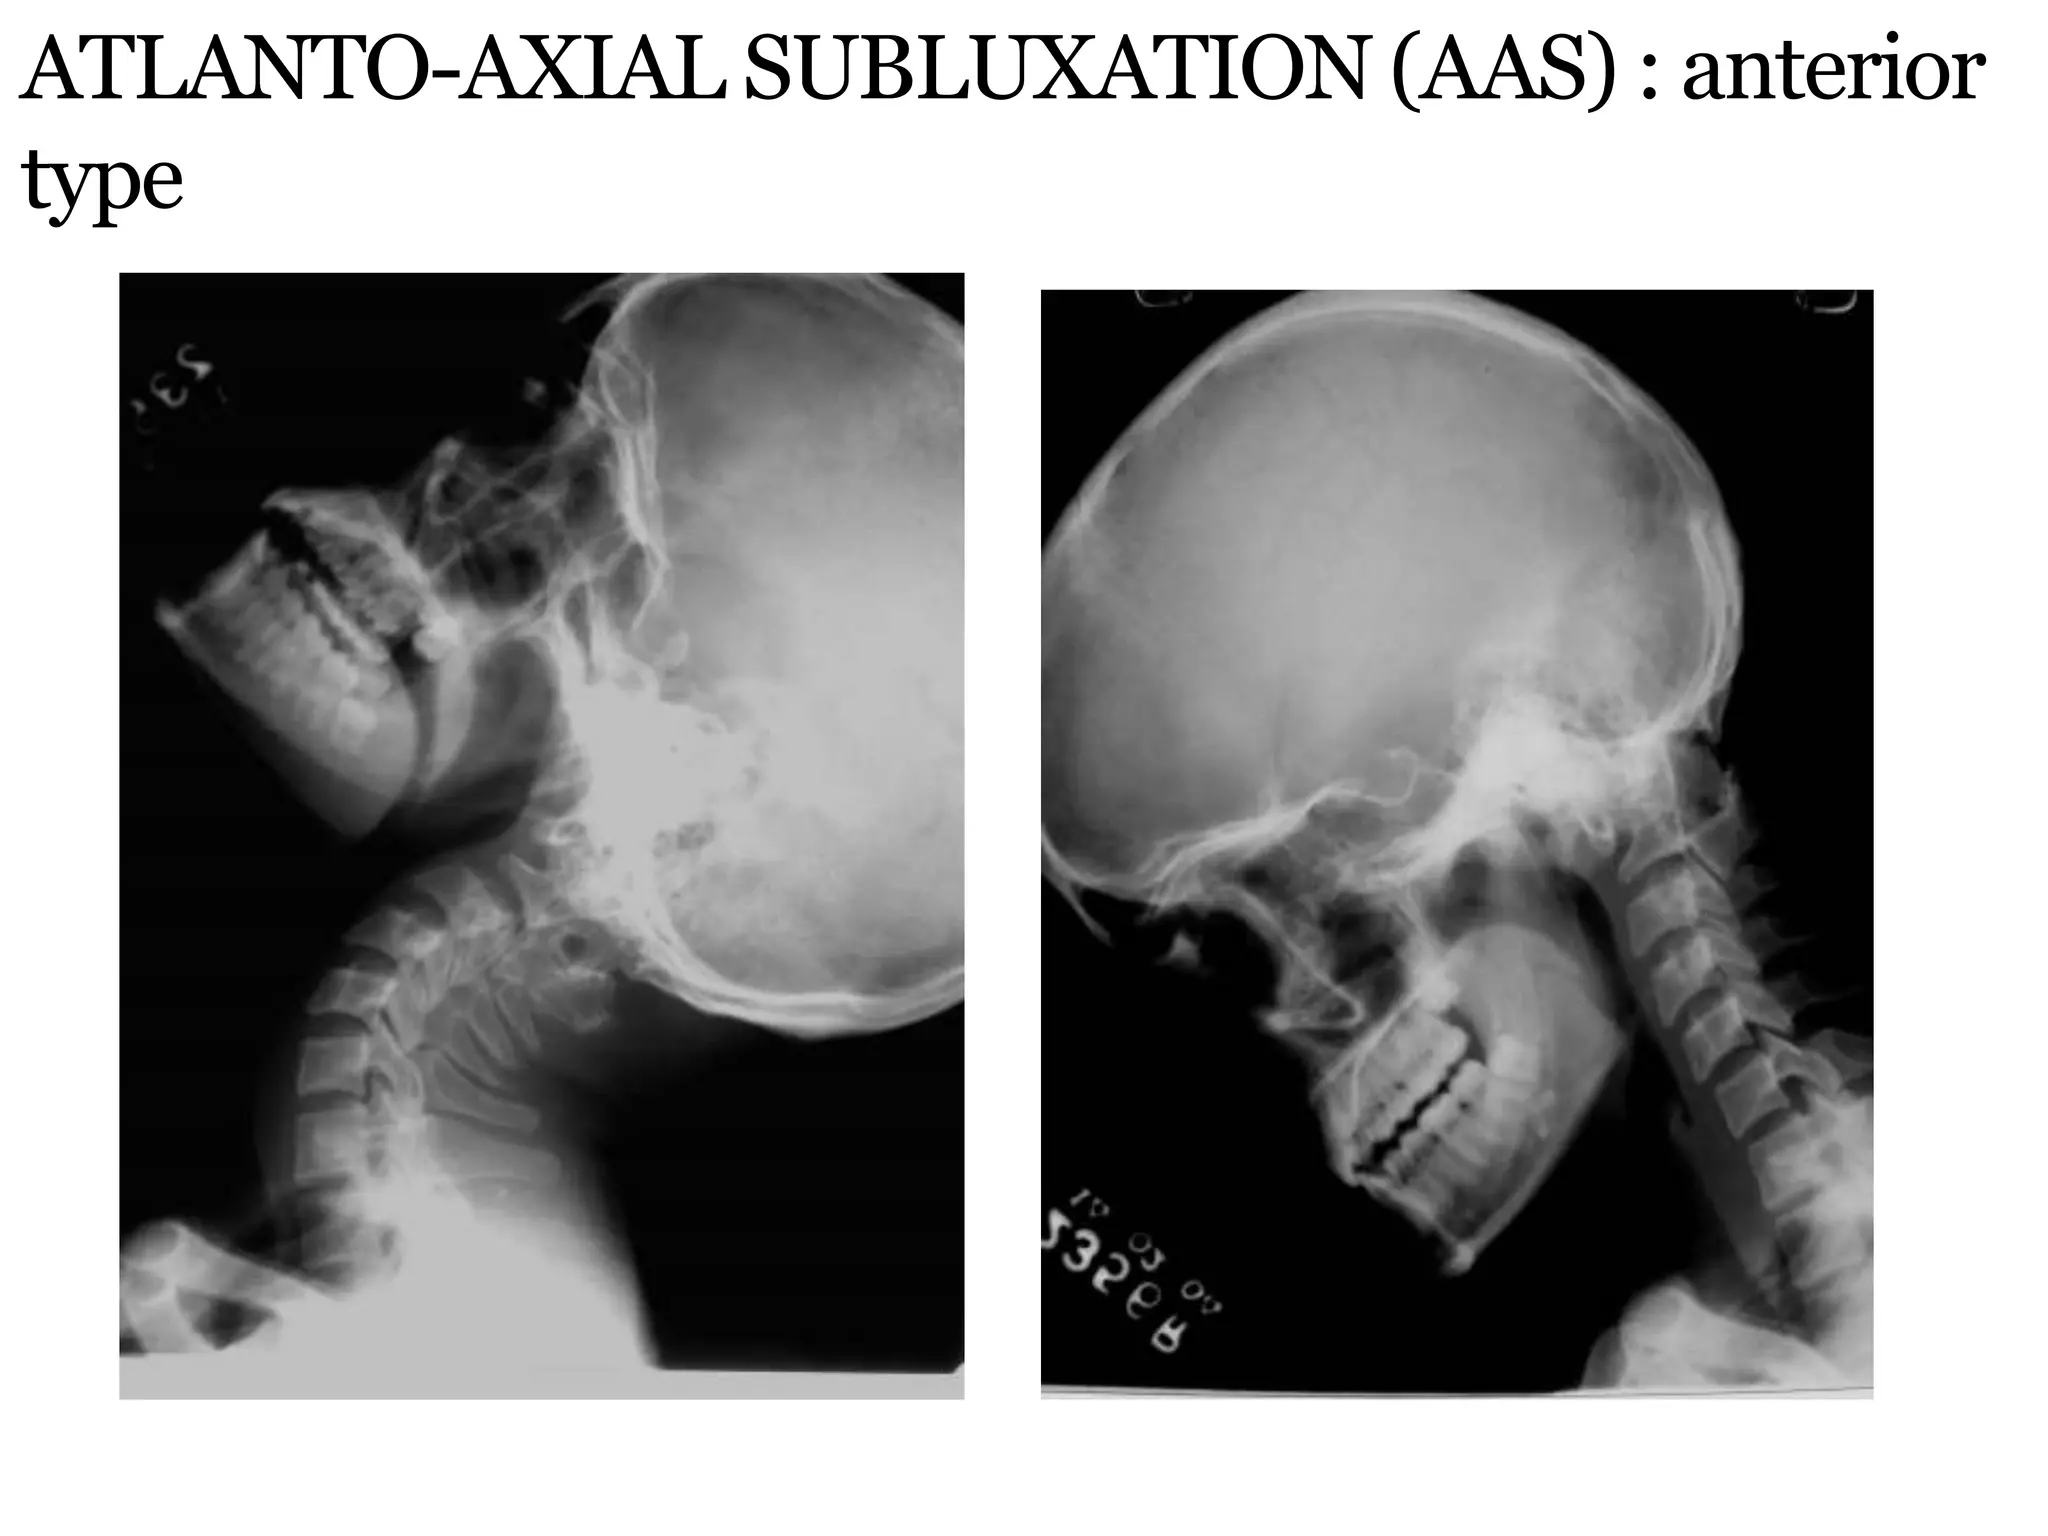

ATLANTO-AXIAL SUBLUXATION (AAS) : anterior

type

 X-rays in neutral position will miss AAS in 48%.

 Controlled flexion views always to be done